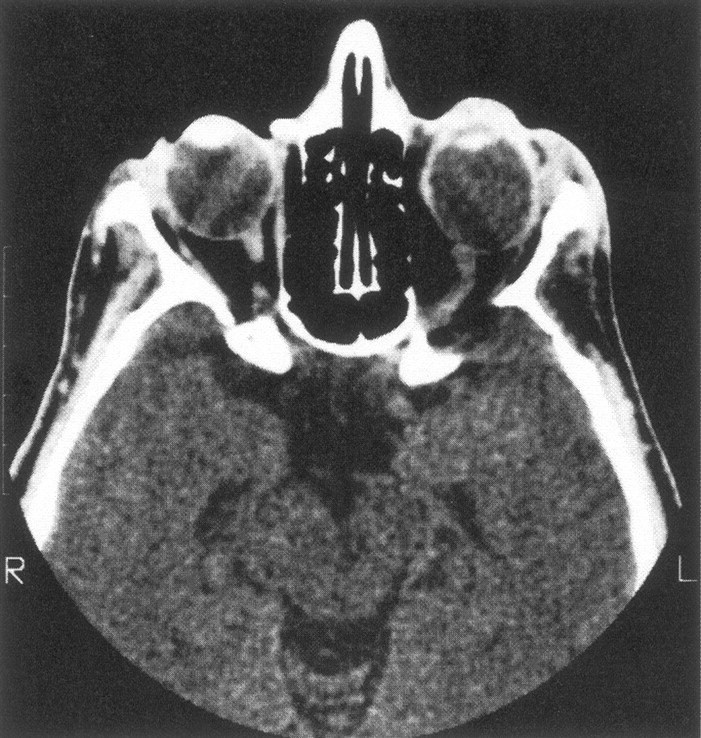

Eighteen patients had decalcification or remodeling of the greater or lesser wing of the sphenoid bone. This process included some remodeling of the sphenoid body and expansion of orbital foramina due to neurofibroma infiltration of orbital nerves. All except one of these patients had extra-axial tumor present in the posterior orbit and pterygoid fossa, contiguous with abnormal bone (Fig 1A). This type of radiologic change was also noted in other areas of the skull, including the jaw, frontal and temporal bones (Fig 1B), and even occipital bone (Fig 1C).

Series of axial CT scans.

A, Infiltration and decalcification of the sphenoid wing underlying neurofibromas.

B, Infiltration and decalcification of the temporal bone underlying neurofibromas.

C, Infiltration and decalcification of the occipital bone underlying neurofibromas.